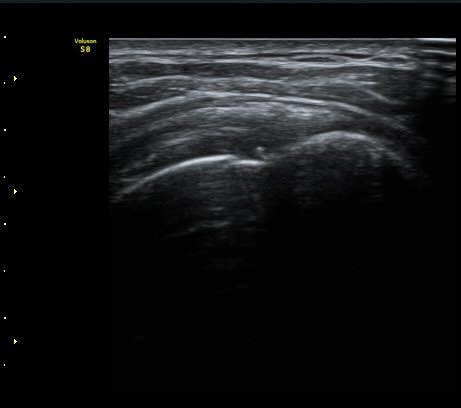

±Ø»ó°Ç Á¾´Ü¸é°Ë»ç¿¡¼­ ´ë°áÀý°ú »ó¿Ï°ñµÎ ÀÌÇàºÎÀ§¿¡ ÇÇÁú°ñ ¿¬¼Ó¼º ¼Ò½ÇÀ» º¸ÀÓ(±×¸² 3, 4, 5)

±Ø»ó°Ç ¿øÀ§ºÎ Ⱦ´Ü¸é°Ë»ç¿¡¼­ ´ë°áÀý°ú »ó¿Ï°ñµÎ ÀÌÇàºÎÀ§¿¡ ÇÇÁú°ñ ¿¬¼Ó¼º ¼Ò½ÇÀ» º¸ÀÓ(±×¸² 7).